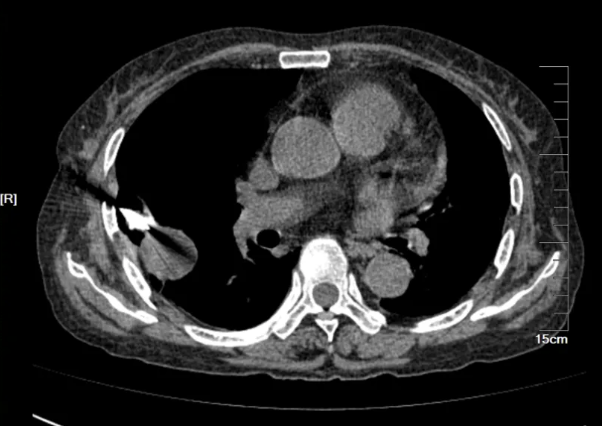

- 胸部CT(图1)(2025-8-15):1、右肺上叶后段空洞性病变(壁厚薄不均,长径约4.9cm,边界尚清,部分边缘稍欠毛糙),双肺多发结节(多发实性、磨玻璃密度结节影,界清,最大者位于右肺下叶背段,长径约1cm,内见空洞),建议CT增强进一步检查。 2、双肺散在炎症、纤维灶;双侧部分支气管轻度扩张;右肺上叶肺大泡。 3、心包部分增厚;主动脉、冠脉多发钙化。 4、腰1椎体楔形压缩。 5、所示双肾形态不规则。

2025年8月31日,患者进食后出现严重恶心、呕吐等胃肠道反应,伴肝酶升高,经予止吐、护胃、静脉营养支持及保肝治疗后未见好转,考虑为复方磺胺甲噁唑片不良反应,遂将其剂量逐步减量至0.48g bid后患者胃肠道反应减轻。2025年9月1日复查血液指标提示BNP及D-二聚体升高,加用利尿、抗凝等对症治疗;复查胸部CT(见图4)显示右肺上叶空洞性病变及右肺下叶背段结节较2025年8月15日影像明显缩小,提示当前抗感染治疗方案有效。

本例患者经约1周抗毛霉治疗后复查胸部CT,提示肺部病灶较前明显缩小,血沉、CRP等炎症指标亦较前下降,提示初始治疗有效。在患者病情趋于稳定后,将静脉抗真菌治疗转换为口服序贯治疗,可选药物包括艾沙康唑或泊沙康唑。鉴于患者肾小球滤过率偏低,我们于2025年9月15日起选用艾沙康唑进行口服序贯治疗。同时嘱患者积极控制危险因素,逐步减量并最终停用糖皮质激素,严格调控血糖。1个月后复查胸部CT(见图9)显示右肺病灶持续缩小、空洞消失;实验室检查提示白细胞、CRP、血沉、降钙素原及IL-6均恢复至正常范围,G试验转为阴性。目前患者继续定期随访,监测影像学及血液学指标。

图9.胸部CT(25-8-15 vs 25-9-1 vs 25-10-13)